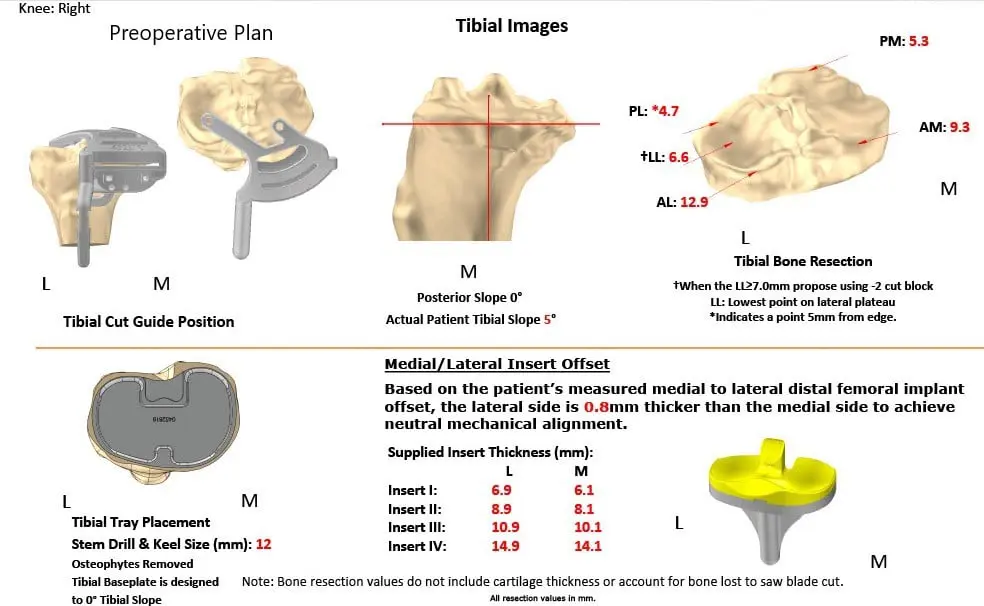

As a part of assessment and planning, a preoperative CAT scan of the lower extremities was obtained a few weeks prior to surgery. Detailed images were acquired for accurate assessment of the patient’s anatomy and biomechanics. Entire data was utilized to construct custom implants and instruments unique for the patient.

Complete Orthopedics patient-specific surgical plan for a customized right total knee replacement in a 73-year-old male with arthritis (scan 2)